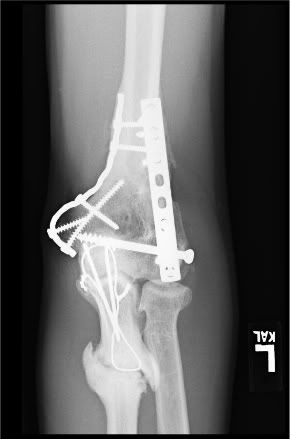

Before going under knife on July 20th, most would tease me with comparisons to Marvel's Wolverine as a result of the comical amount of surgical hardware I have holding my frame together.

Hunky superhero jokes aside, I've been living with several left ulna "non-unions" since 2005 resulting in "overactive bone growth" in my arm.